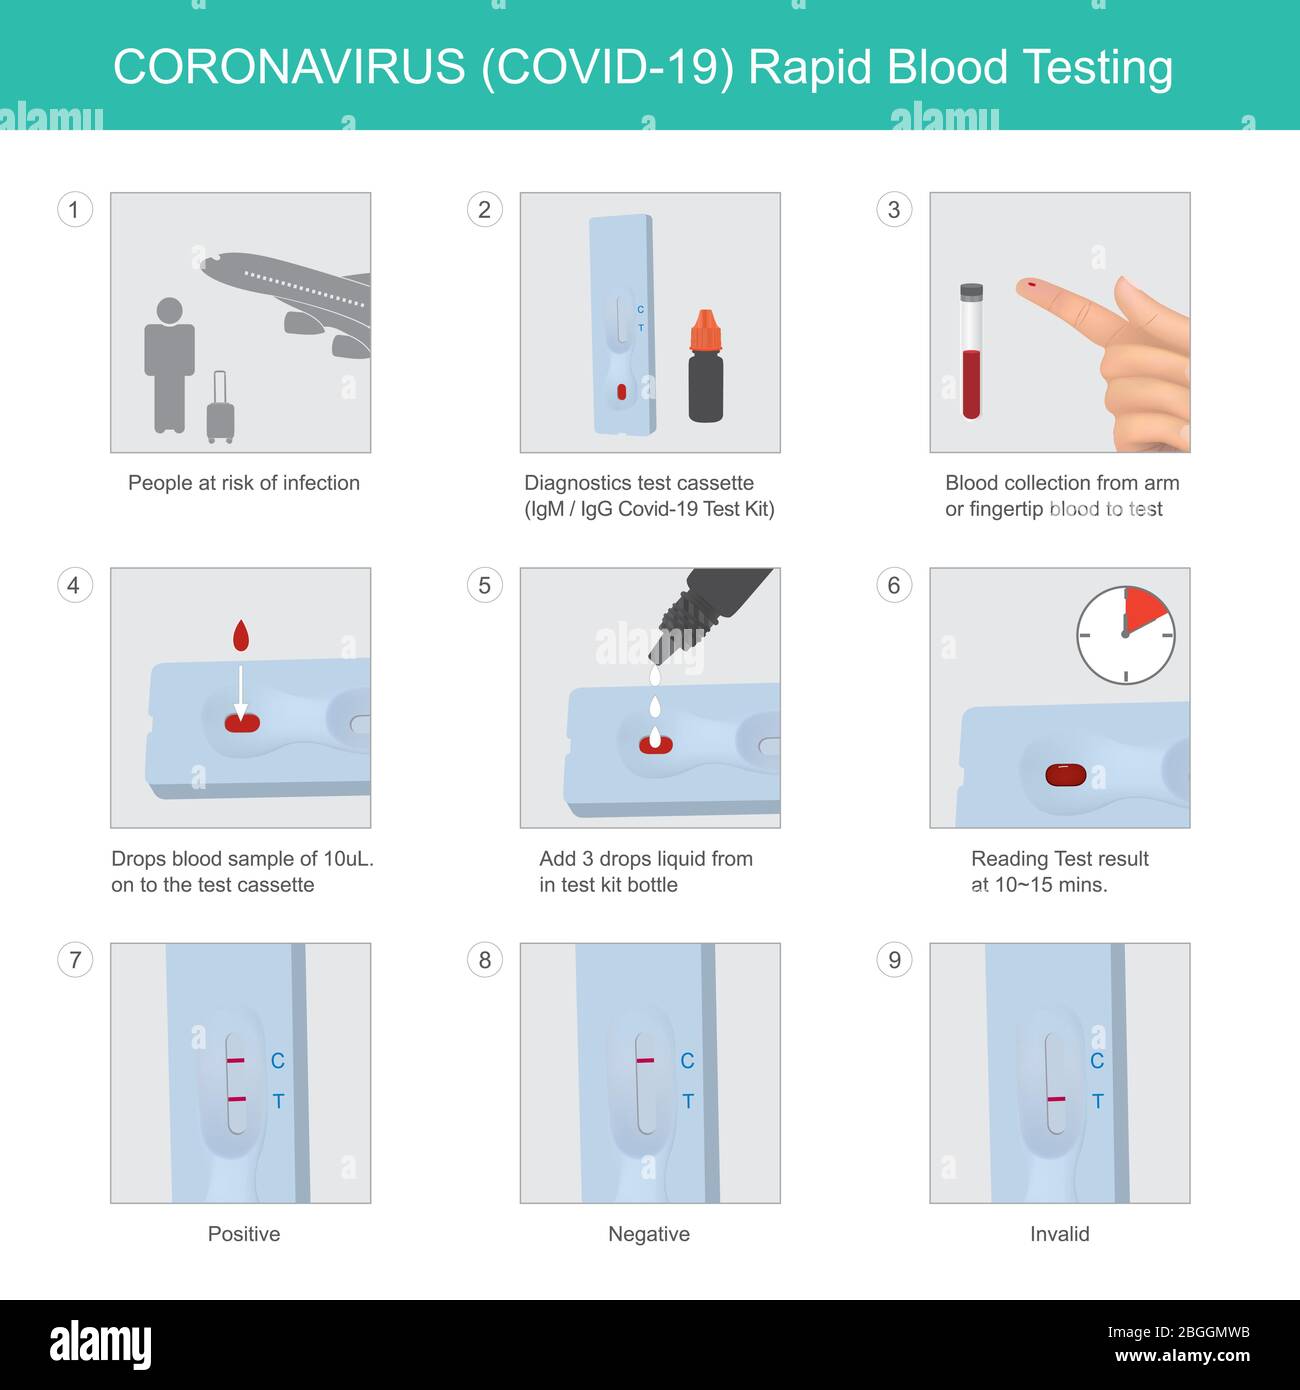

ANALISI del sangue rapida PER IL CORONAVIRUS. Metodo utilizzato per il kit di analisi PER CORONAVIRUS (COVID-19) in persone a rischio di infezione con risultati rapidi. Illustrazione Vettorialehttps://www.alamy.it/image-license-details/?v=1https://www.alamy.it/analisi-del-sangue-rapida-per-il-coronavirus-metodo-utilizzato-per-il-kit-di-analisi-per-coronavirus-covid-19-in-persone-a-rischio-di-infezione-con-risultati-rapidi-image354409479.html

ANALISI del sangue rapida PER IL CORONAVIRUS. Metodo utilizzato per il kit di analisi PER CORONAVIRUS (COVID-19) in persone a rischio di infezione con risultati rapidi. Illustrazione Vettorialehttps://www.alamy.it/image-license-details/?v=1https://www.alamy.it/analisi-del-sangue-rapida-per-il-coronavirus-metodo-utilizzato-per-il-kit-di-analisi-per-coronavirus-covid-19-in-persone-a-rischio-di-infezione-con-risultati-rapidi-image354409479.htmlRF2BGGMWB–ANALISI del sangue rapida PER IL CORONAVIRUS. Metodo utilizzato per il kit di analisi PER CORONAVIRUS (COVID-19) in persone a rischio di infezione con risultati rapidi.